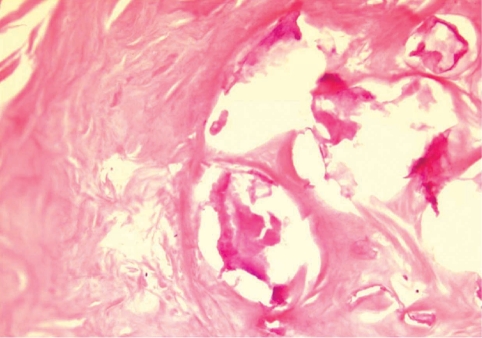

During the surgery, a small longitudinal incision was made on the upper portion of the elongated mass. A white-shiny, synovium-like piece of tissue popped out through the incision, and this was determined to be a sparganum that measured 18 cm in length and 0.5 cm in width, wriggling after removal from the patient. It was diminished to 13 cm in length and 12 mm in width after fixation in 10% formalin (Fig. 3). The calcified foci near the calf were also removed, and the pathologic examination revealed tubular tracts in the subcutaneous tissue (Fig. 4). These tracts possibly represented the pathway along which the larvae had passed. The tracks showed multiple, benign fibrocalcific nodular lesions with a few skeletal muscle fascicles, and the lesions were markedly degenerated (Fig. 5). The patient was a farmer, and she denied ingesting snake or frog meat, but she admitted drinking untreated mineral water from a local mountain. On the third postoperative day, the patient was discharged and followed up uneventfully.

In a patient with sparganosis, the characteristic host tissue reaction is an elongated tract-like cavity through which a larva has passed [16]. The sequential pathologic changes of sparganosis were reported as the followings; an inflammatory cell infiltration develops in the first week after the inoculation of the larvae into the soft tissue, tunnel-like structures appeared 2 weeks later, and a fibroblast proliferation appears about 4 weeks after that and this lasts as long as 6 months. If the larva migrates and then dies, the tunnels with inflammatory foci are replaced by granulation tissue [17]. In the present case, the tract was replaced by granulation tissue and calcium nodules were deposited on it. Hence, the tract of this case seems to have been formed at least years ago, supporting an old age of the present worm. However, the comparison of pathologic findings between the present case and other old sparganosis was not possible since the histological examinations of sparganosis were mostly done only on the nodule containing the larva, not the migration tract. For example, histological examination of a 19-year old sparganosis revealed suppurative, granulomatous dermatitis and panniculitis with spaces containing cross-sections of a cestode larval worm [10].